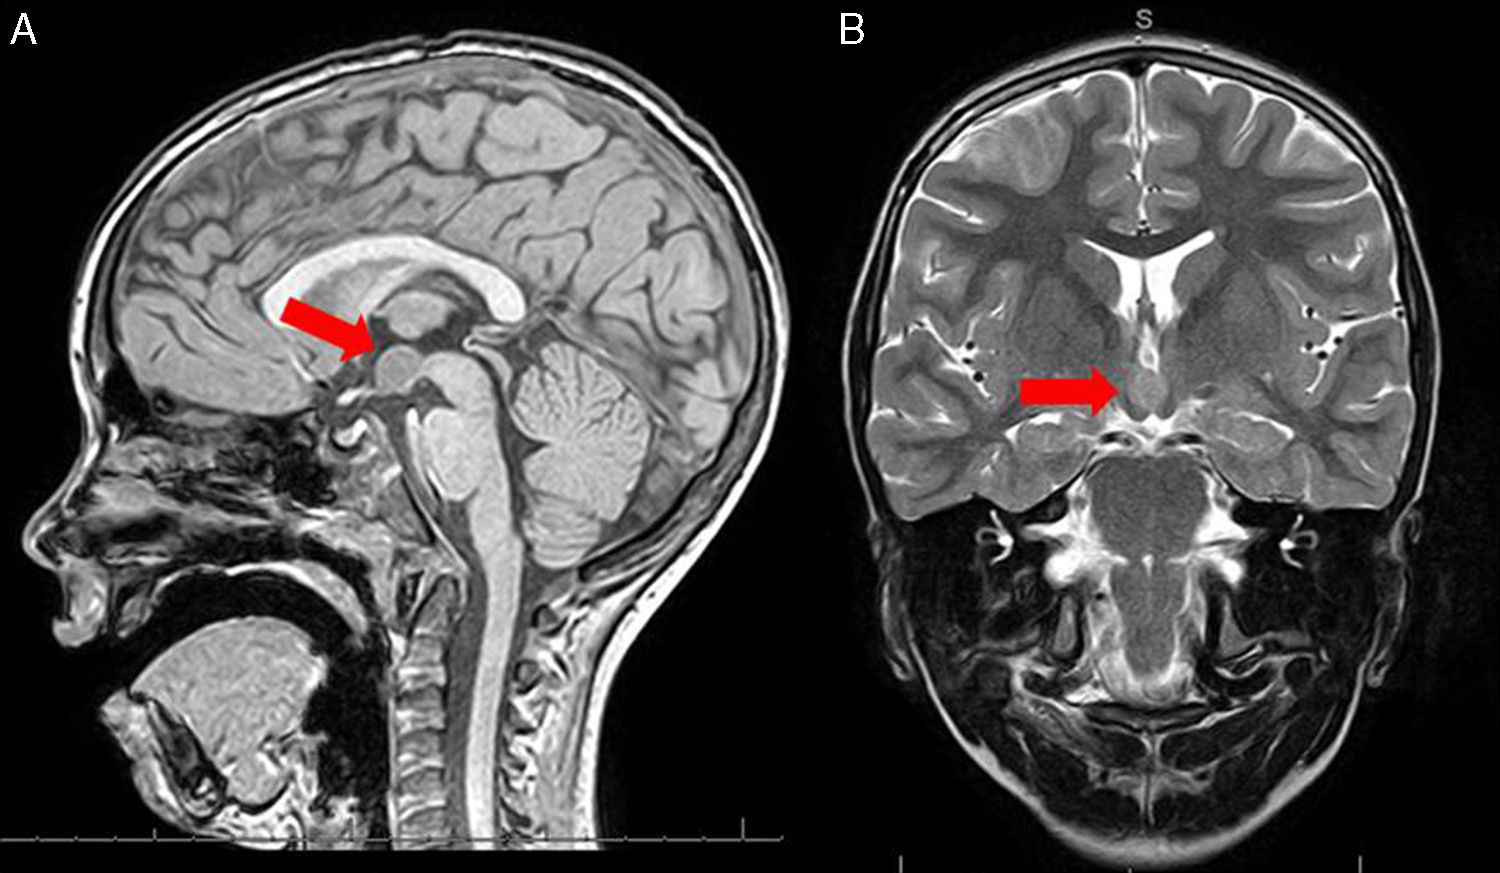

Гамартома удаление

Гамартома удаление 112 фото